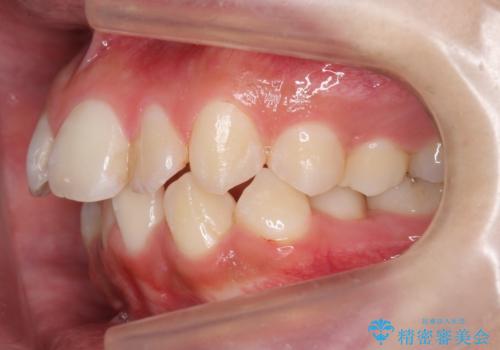

- 前歯のがたつきを主訴に来院。

顔が小さく、顎に大きな歯が入りきらない状態でした。

抜歯してワイヤー矯正を行いました。